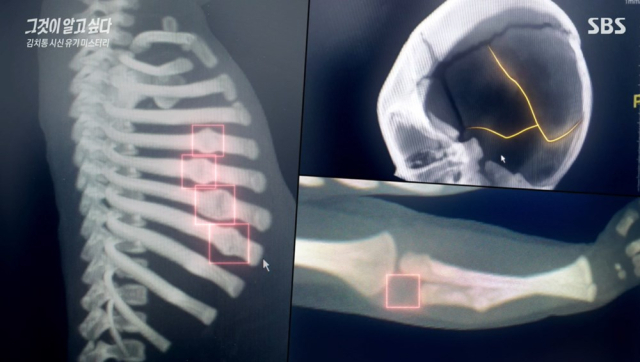

2015년 12월 서씨와 최씨 사이에서 태어난 B군은 생후 100일 무렵 자다가 엎어져 숨진 것으로 추정된다며 병원으로 이송됐다. 심정지 상태로 응급실에 실려온 B군을 대상으로 엑스레이 촬영한 결과 두개골에 큰 골절이 있었고, 갈비뼈와 팔뼈에서도 골절 후 치유된 흔적이 발견됐다.

당시 부모는 "아이가 침대에서 떨어져 생긴 골절"이라고 주장했다. 아이의 팔에 있던 골절은 "첫째가 우연히 밟아서 생긴 것"이라고 설명했다.

하지만 전문가의 분석은 달랐다. 전문가들은 "이것은 학대, 저 정도로 때리면 죽지 않을까 이런 정도의 충격들이 가해진 것으로 보인다"고 판단했다. 특히 두개골 골절은 성인 남성이 머리뼈가 고정된 상태에서 강하게 내리쳤을 때 가능하다는 분석이 나왔다. 즉, 프로 권투 선수가 날리는 주먹에 가까운 외력이 있어야만 이러한 골절이 생긴다는 것.

그럼에도 당시 부검 결과는 사인 불명으로 결론났다. 골절이 학대 정황을 시사하지만, 직접적인 사망 원인인지 단정할 수 없다는 이유에서였다. 서씨와 최씨는 학대에 대한 거짓말 탐지기 테스트를 완강하게 거부했고, 경찰도 사건을 결국 내사 종결됐다.